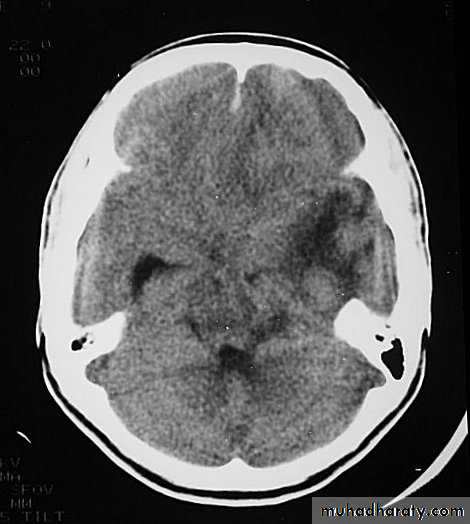

They can increase both brain metabolism and blood flow, therefore increasing intracranial pressure.5. Hydrocephalus

a. Acutely due to obstruction of CSF outflow due to intraventricular blood.b. Delayed post-traumatic communicating hydrocephalus due to impaired CSF reabsorption following traumatic subarachnoid haemorrhage

Intraventricular blood can lead to Hydrocephalus